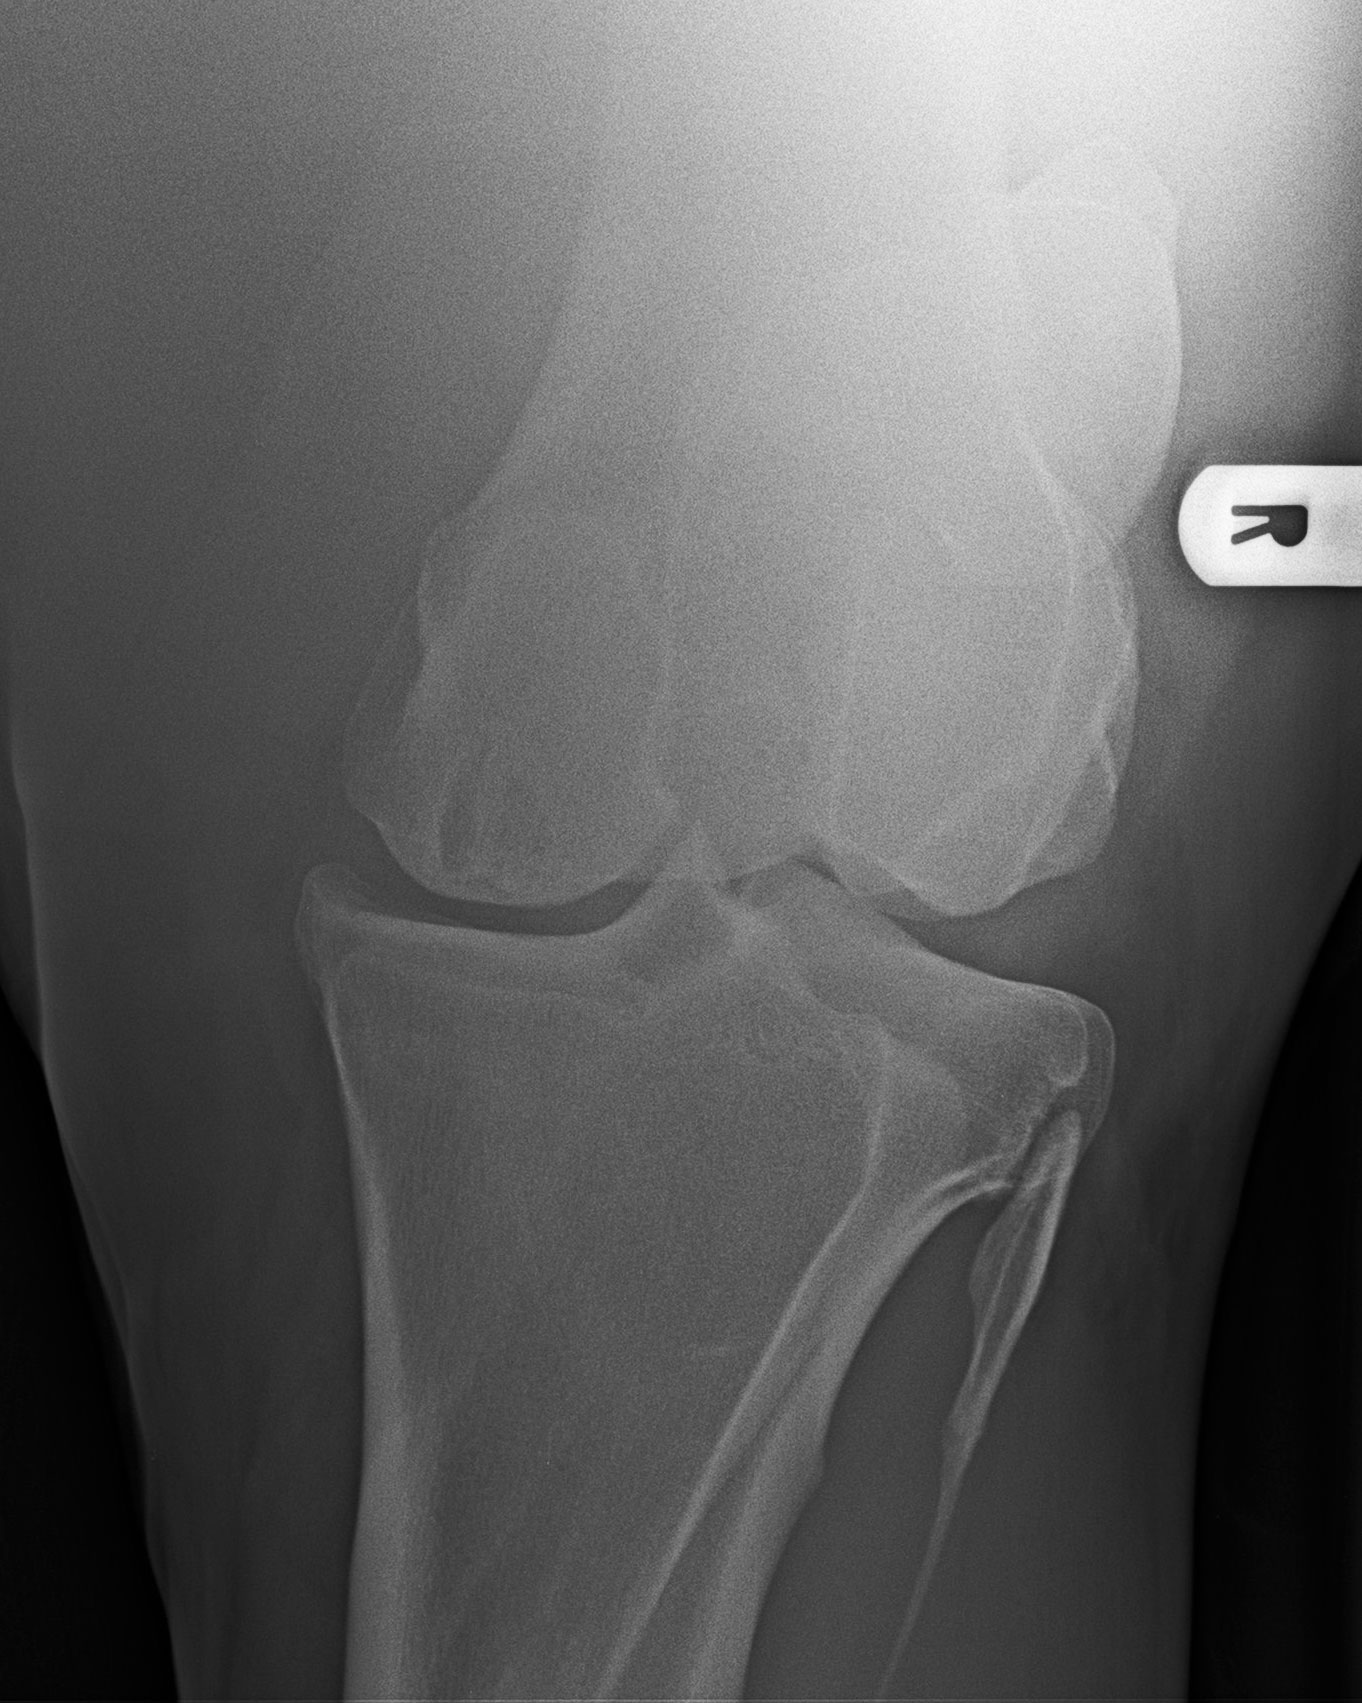

Kniegelenk - 0°-Aufnahme